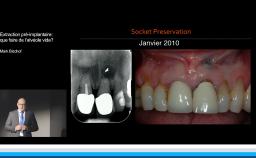

Edentement au secteur anterieur: le défi pour une esthetique optimale

A partir de la description des facteurs de risque esthétique du bloc incisivo-canin maxillaire, de la présence d’os et de gencive autour des implants, le conférencier présente une succession de cas cliniques décrivant ses procédures chirurgicales et prothétiques.

• de déterminer le bon timing de chirurgie implantaire post extractionnelle

• de réfléchir sur la préservation à moyen-long terme de l’os autour des implants

• Ridge Preservation